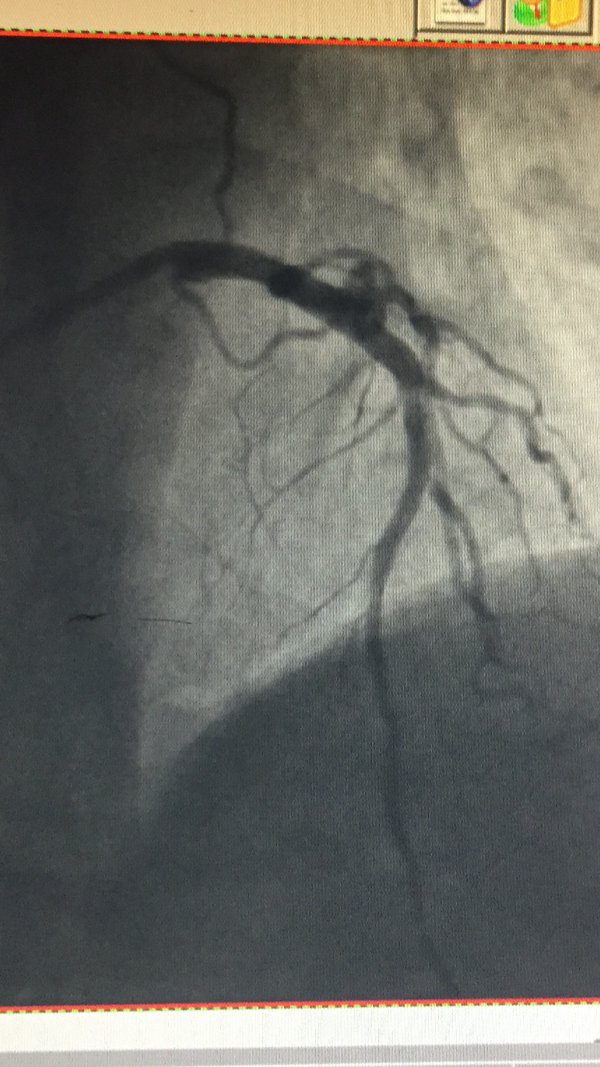

左主干中段狭窄90%

冠脉造影提示:左主干中段狭窄90%,患者随时可能出现猝死的危险,且药物治疗根本无效。

1月4日下午14点48分,虞城县人民医院导管室,病人局部麻醉后,高主任联合郑州大学一附院心血管内科赵荫涛教授从容而谨慎地开始了左主干介入手术。手术采用右手桡动脉入径,安置导丝...短短32分钟紧张而默契的操作,成功解决患者生命威胁。目前患者胸闷症状完全消失,各项生命体征平稳,正逐步康复中。